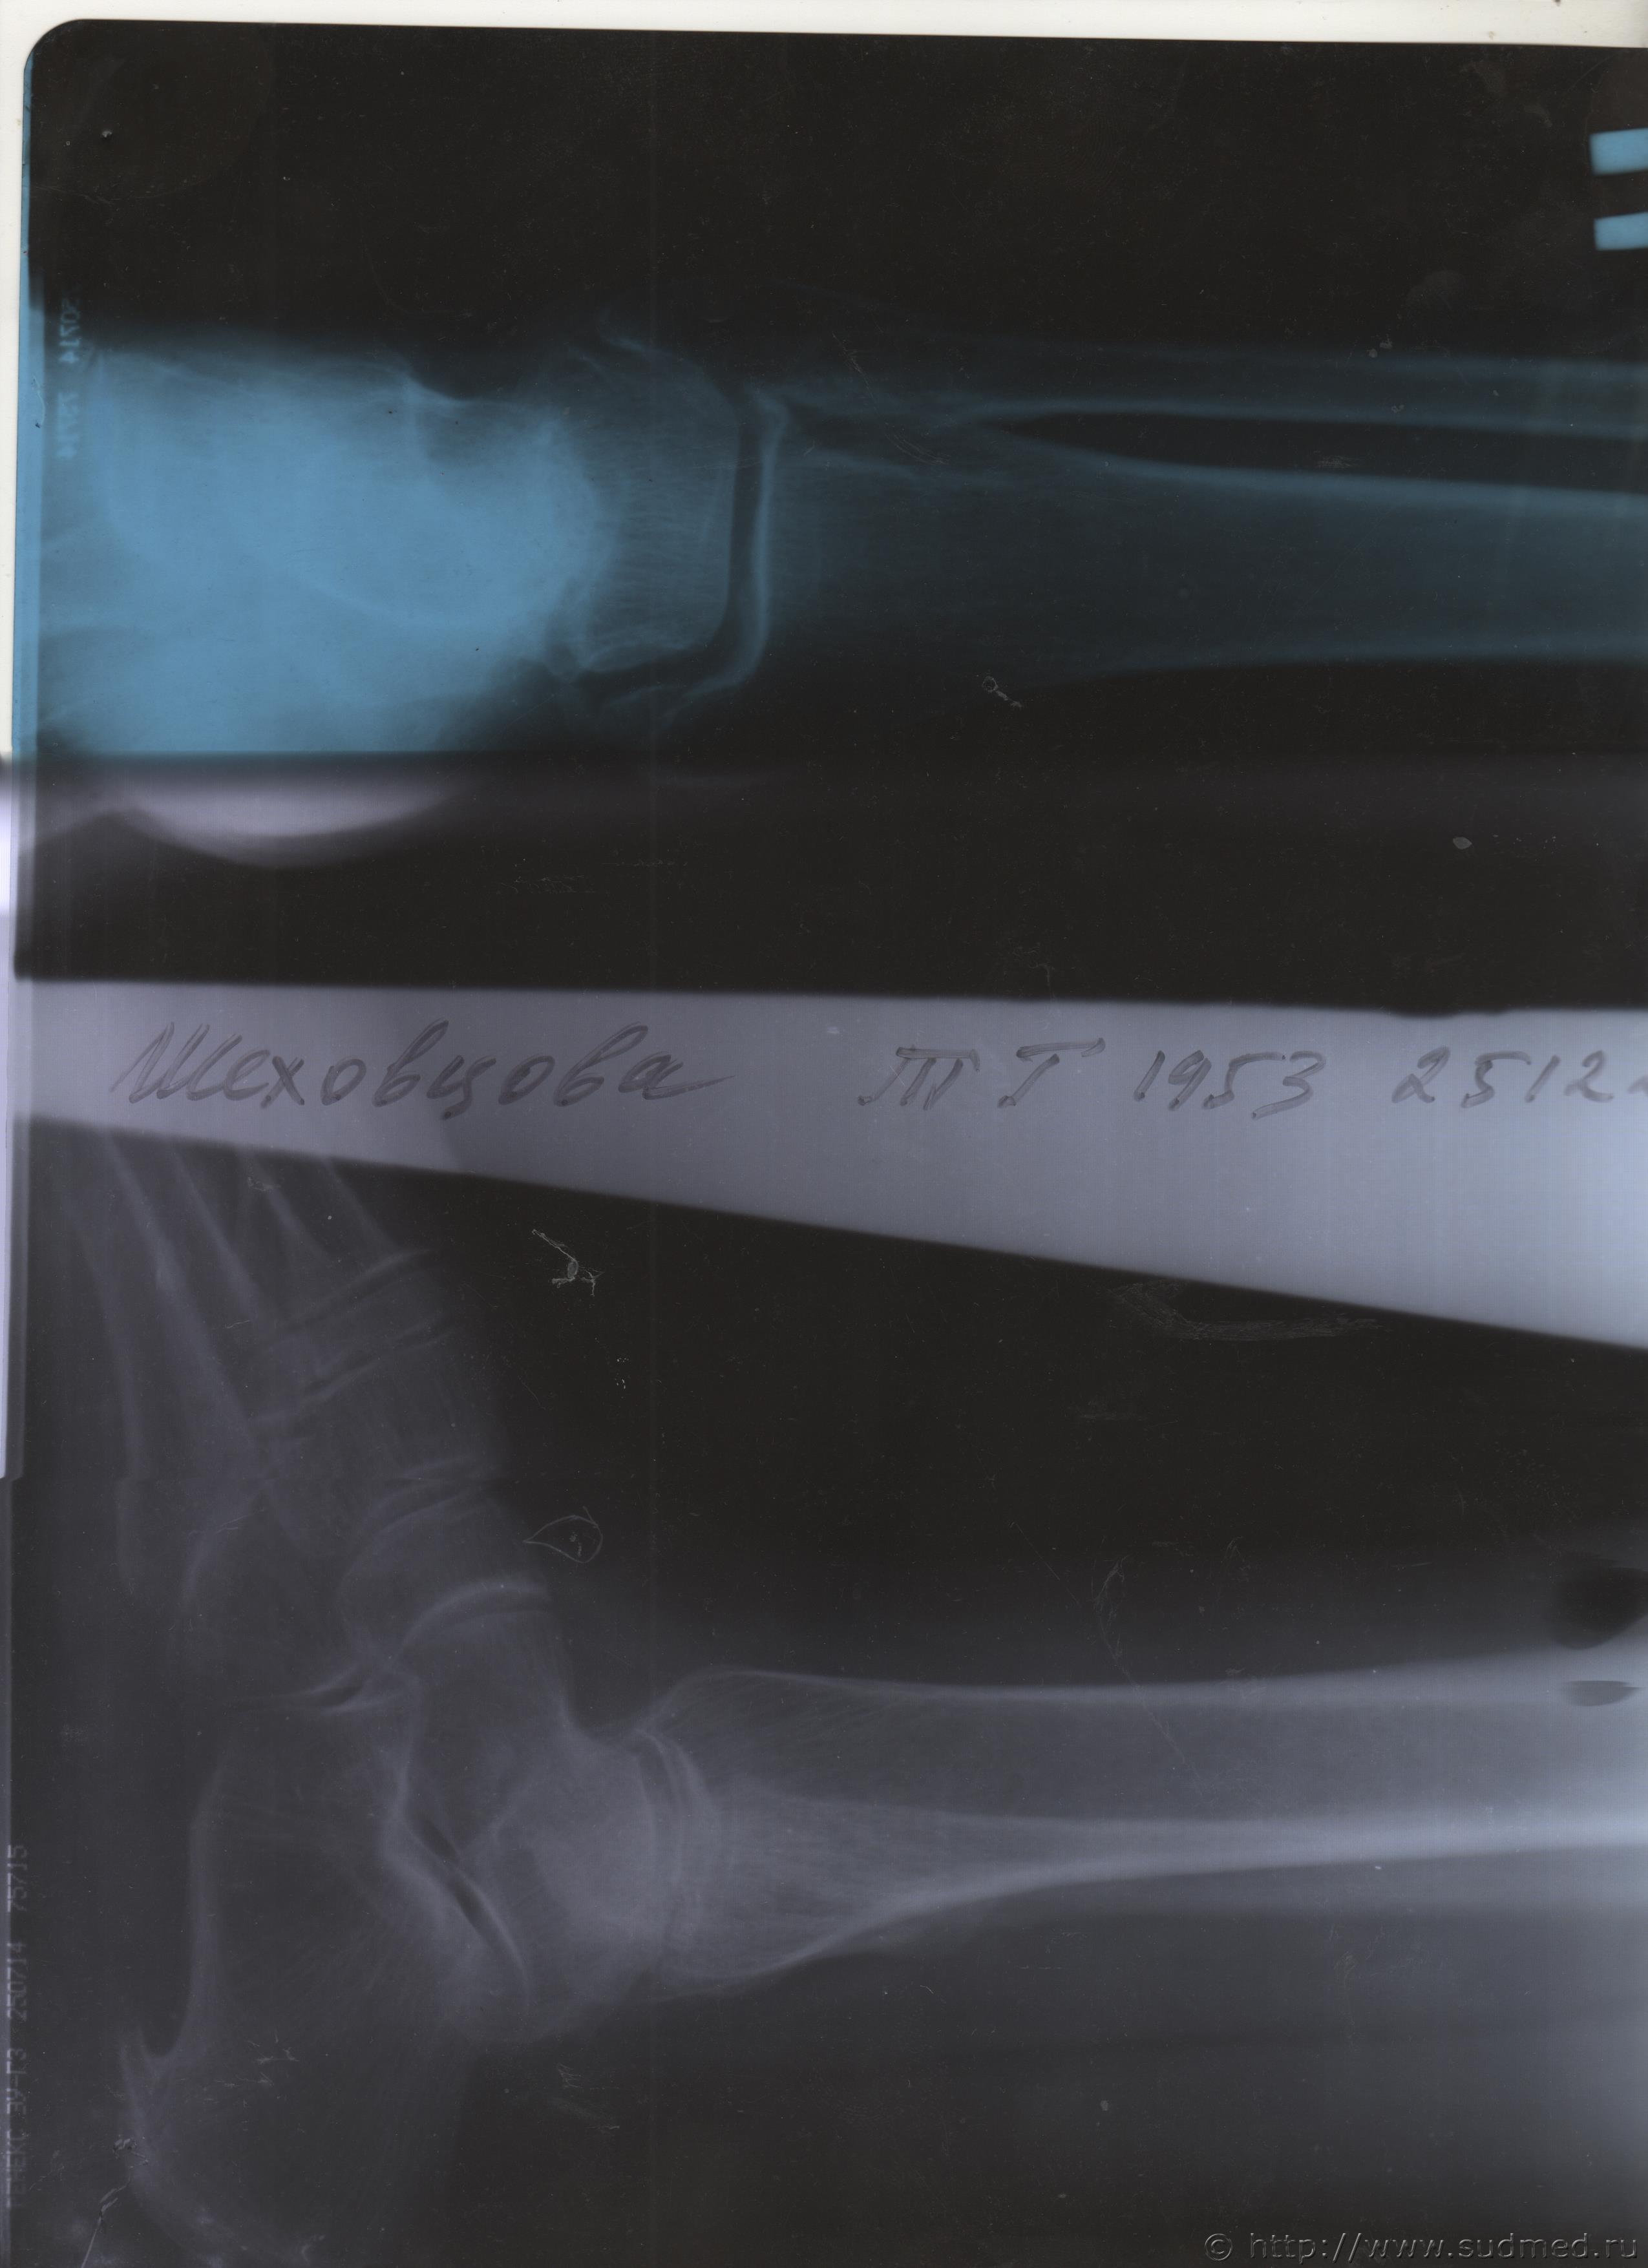

06.07.2015 г. при обращении в горбольницу мне выдали не описанный снимок( все рентгенологи были в отпуске) и справку № 4379 от 06.07.15 г. где диагноз: закрытый 2-х лодыжечный перелом правой голени без смещения. Копию справки прилагаю

За все 12 месяцев, что была на больничном, 8 раз делали снимки травмированной ноги и все заключения именно : «закрытый 2-х лодыжечный перелом правой голени без смещения».

После того, как был поставлен диагноз : «компрессионный перелом L2 позвонка поясничного отдела позвоночника». Амбулаторная мед карта, была украдена из кабинета врача травматолога. При восстановлении мед карты( в марте 2016 г.), врачом травматологом была взята копия справки от 06.07.15 г.из приемного отделения горбольницы. Справка № 4379 ( дубликат), диагноз : «закрытый 2-х лодыжечный перелом правой голени без смещения».

Посмотрите, это снимки за 12 месяцев.

Уважаемая Татьяна! По представленным Вами снимкам ничего сказать нельзя: нет маркировки даты каждого снимка (поэтому, невозможно их сравнивать друг с другом и соотносить с датой травмы), исследование непосредственно пленок гораздо более информативно, чем анализ представленных изображений (детали костной структуры в зоне перелома практически не видны).

Рекомендую проконсультировать все эти снимки у высококвалифицированного рентгенолога. Далее - по ситуации, т.е. в зависимости от его мнения. В любом случае, есть формальные основания для назначения дополнительной экспертизы, т.к., судя по представленному Вами фрагменту заключения эксперта, на экспертизу не были предоставлены все мед.документы с данными о лечении предъявляемой травмы (Вы пишете, что рентгенограммы делались на протяжении 12 месяцев, полагаю, что Вы и врачами наблюдались в течение этого срока, т.е. велась мед.карта).